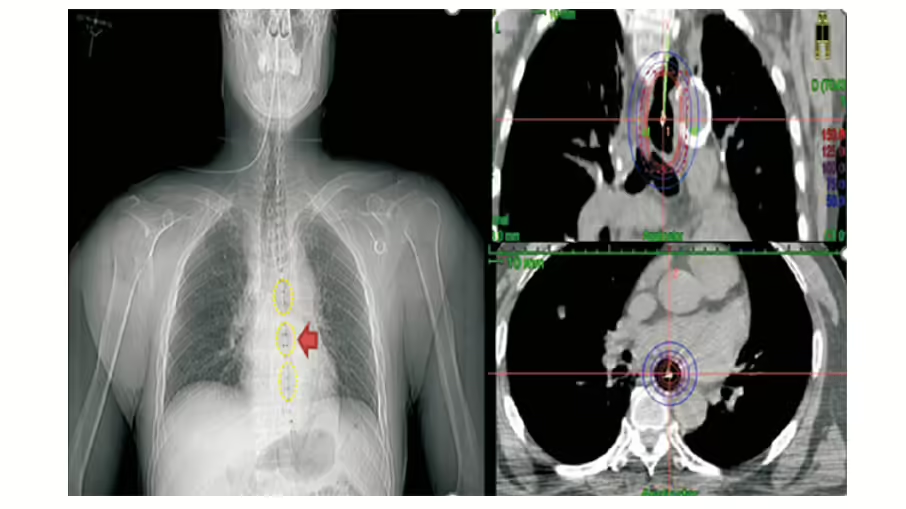

食道癌放射治療,以照射來源來區分,從身體外部用儀器照進體內的叫外部照射,藉由導管把能量射源放進體內運到食道腫瘤旁集中治療,叫「體內近接治療」。

而針對不能切除的原位癌或早期食道癌,或是治療後有殘餘病灶,或是治療過後局部復發造成食道狹窄的病人,現在可使用新式食道置放器的近接治療,來降低局部復發,並減少腫瘤體積,讓病人可以順利進食。綜合外部照射及近接治療,可以讓癌症控制更久,治療更順利,進食更安心。

圖說:「近接治療」是屬於精準放射治療的一種,透過導管將放射性物質運送至腫瘤旁照射,適用於局部殘餘的病灶,或是用來減少腫瘤體積, 使病患可以進食。